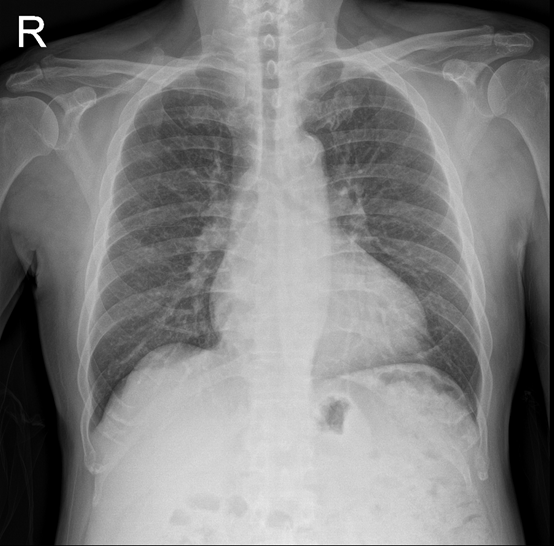

A 59-year-old man with dyspnea on exertion for a month was admitted for scheduled percutaneous coronary intervention. His medical history included hypertension, hyperlipidemia, and type 2 diabetes. He also had 2-vessel coronary artery disease with a bare metal stent each in the right coronary and the left anterior descending arteries. Physical examination was unremarkable except for being slightly overweight; ECG showed sinus bradycardia and chest x-ray excluded severe pulmonary disease.